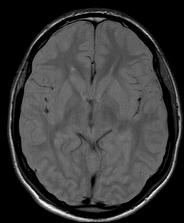

Specific suppression of free water is also possible (e.g.: cerebrospinal fluid) with FLAIR (Fluid-Attenuatited Inversion Recovery) sequence.

- T1W image: (brain, sagitta slice, arachnid cyst)